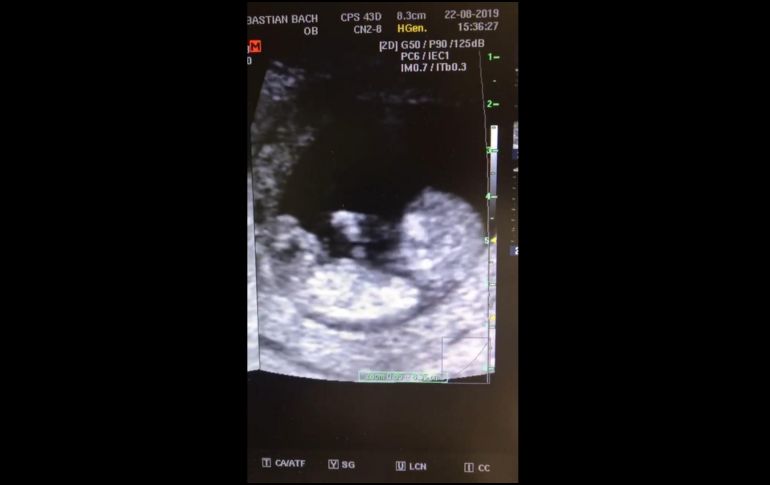

Un video ha causado sensación en las redes sociales. Se trata de un ultrasonido en el que se observa a un bebé de 12 semanas de gestación "jugando a la resbaladilla" en el vientre de su madre, según lo manifestó Alejandro Acosta Aguilar, el médico que difundió el material.

En el video se observa cómo el bebé se impulsa en repetidas ocasiones con sus pies para "saltar" en el seno de su madre y luego deslizarse lentamente, para repetir la acción una y otra vez, mientras se alcanza a reconocer el cordón umbilical que lo une a la placenta.

De acuerdo a la información que se proporciona en el "post" de Facebook, sucedió en una unidad médica ubicada en el municipio de Zapopan el pasado 22 de agosto.